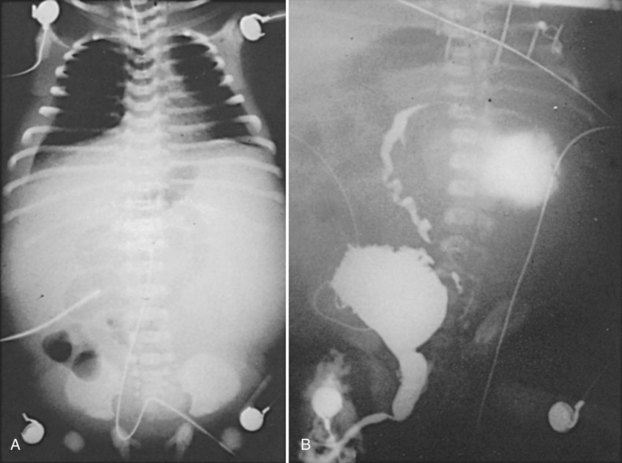

Forty percent of neonatal ascites is caused by urinary conditions (Fig. 126–6) (Adzick et al, 1985). Urinary ascites occurs when high intraluminal pressure forces urine to extravasate from the kidney, usually across a renal fornix. Urine then enters the retroperitoneum and travels across the peritoneum as a transudate. If aspirated from the peritoneal cavity, the ascites or extravasated urine contains electrolyte and creatinine levels similar to serum. The urine within the peritoneum is subject to the large absorptive mesothelial surface that quickly normalizes these values, masking the identity of ascitic fluid as urine. The diagnosis of urinary ascites may be difficult and may require definitive upper tract drainage in the form of nephrostomy tubes in order to establish the etiology of the ascites and allow its resolution. Urinary ascites in the case of distal obstruction may serve to lower urinary pressures and offer some protection to the developing kidneys (Conner et al, 1988).

Figure 126–6 A, Abdominal radiograph shows the ground-glass appearance of an infant with ascites. B, Voiding cystourethrogram demonstrates reflux of contrast material, which is then seen extravasating into a urinoma and later flowing into the abdominal cavity as urinary ascites.

(From Gonzales ED. Posterior urethral valves and other ureteral anomalies. In: Walsh PC, Retik AB, Vaughan ED, Wein AJ, editors. Campbell’s urology. 8th ed. Philadelphia: WB Saunders; 2002.)

Patel and colleagues (2003) reviewed a large group of 615 valve patients and analyzed the protective effect of ascites compared with unilateral and bilateral urinomas. The authors found that the kidney associated with a unilateral urinoma is often impaired. Bilateral urinomas are associated with good renal function, but urinary ascites alone has a poorer prognosis. The GFR of patients with urinary ascites alone was 29 mL/min per 1.73 m3 compared with 36 mL for boys with unilateral urinoma alone, 74 mL for boys with urinoma plus ascites, and 104 mL for bilateral urinomas.